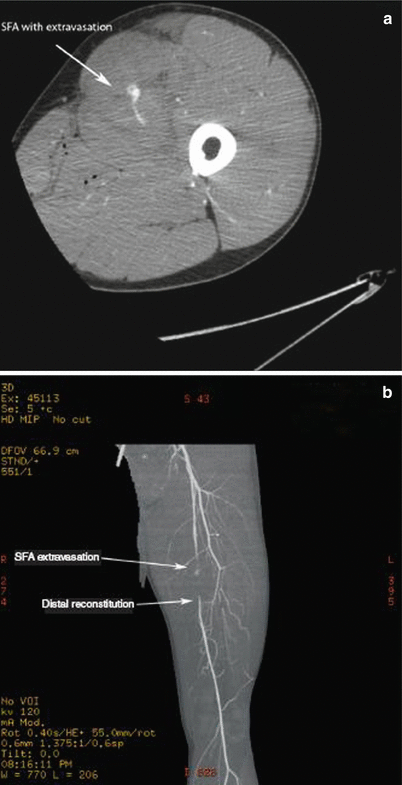

Fig. 16.10

(a) Gunshot wound to the left lower extremity with evidence of contrast extravasation in the territory of superficial femoral artery (SFA). Patient required vascular repair using vein graft. (b) Vascular reconstruction demonstrating SFA injury with extravasation as well as distal reconstitution of vessel

CT angiography represents a step forward in the workup of stable patients with extremity injures concerning for vascular injury without hard signs. While it only allows for diagnosis, it does so without many of the potential hazards associated with conventional angiography. With its high sensitivity and specificity and low potential for complications compared to conventional angiography, CT angiography offers an excellent radiographic tool for the rapid diagnosis of peripheral vascular injuries. Once the presence of CT angiographic signs of arterial injury, including active extravasation, pseudoaneurysm formation, abrupt narrowing of a vessel, loss or opacification of an arterial segment, or arteriovenous fistula, has been confirmed, either operative intervention, interventional radiographic intervention, or appropriate observation can be undertaken as dictated by the injury. It is important to note that the ability to detect injury is potentially related to the resolving power of the scanner. One author notes that the lack of intimal injuries detected over a 3-year period at their institution may have been related to the limited resolution of the four-row multidetector CT scanner used at the time.